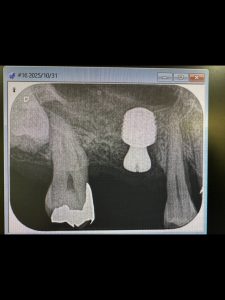

朝から、インプラントオペ

残存骨0.5から2ミリ内の難儀なリフティング

予想に反し、計測値も非常に良く😱

難なく30分で終わり💪